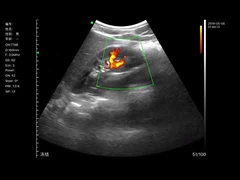

Calidad Escáner de ultrasonido portátil, analizador del ultrasonido del PDA Fabricante de China

Ultrasound scanner